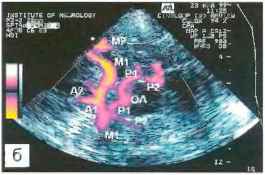

Узи интракраниальных артерий

Узи интракраниальных артерий 112 фото